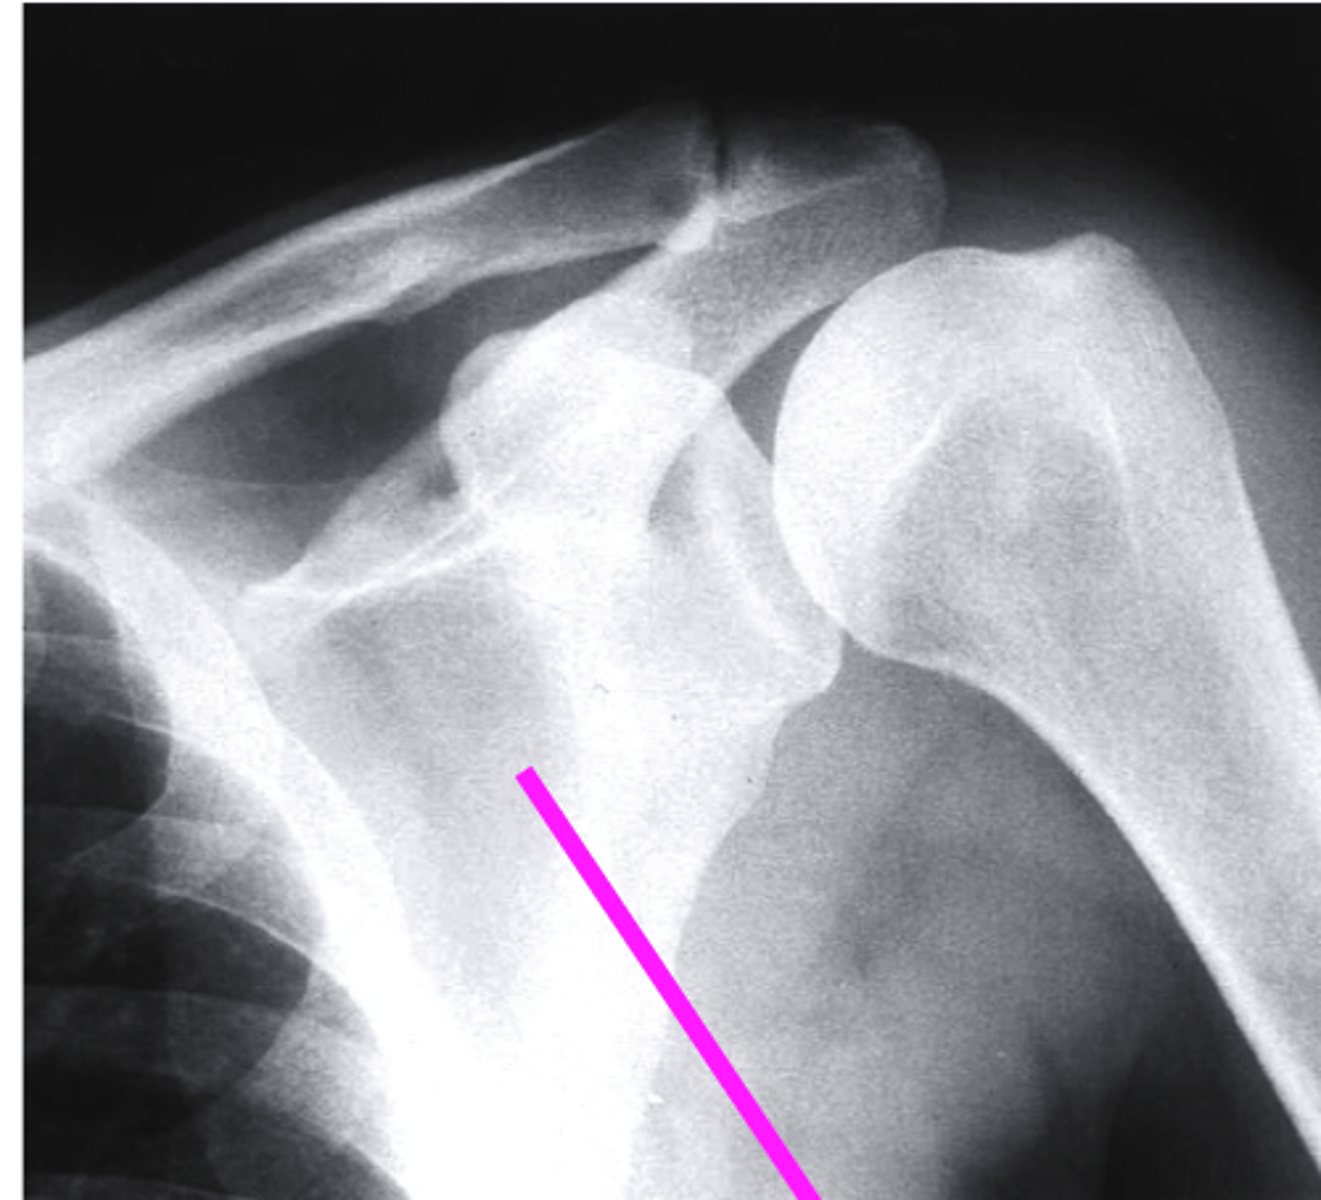

AP + IR

what view is this?

clavicle

what does the pink line point to?

spine of scapula

coracoid process

glenoid fossa of scapula

AC joint

acromion

Humeral Head

lesser tubercle